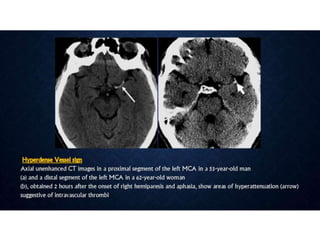

• • Is there hemorrhage that explains the symptoms or excludes lytic

• • Is there intravascular thrombus that can be targeted for thrombolysis?